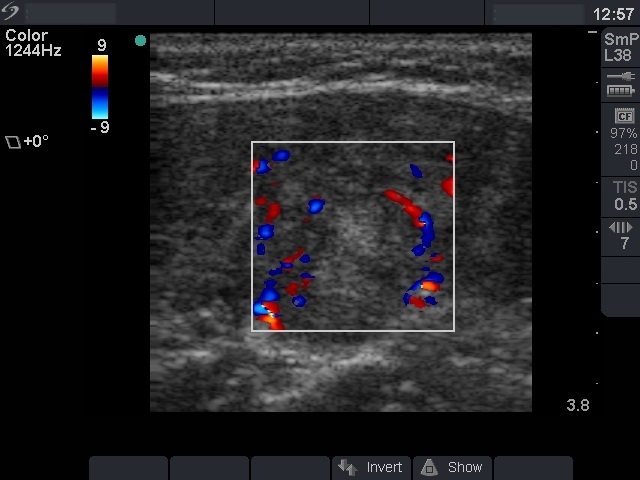

Chronic lymphocytic thyroiditis - Case 54. (ultrasonographic picture 6)

Left lobe, longitudinal view, color Doppler mode. The vascularization is not specific.